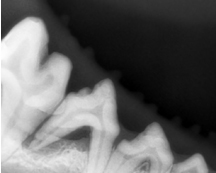

- 치과 X-ray

특히 고양이의 치주질환의 경우 전체 치아가 영향을 받아 통증을 매우 심하게 유발하고 발치를 해야하는 경우도 많아 6~12 개월 간격으로 정기적인 치아 상태 확인 및 스켈링이 필요하며, 심각한 치아 및 치근의 손상이 의심된다면 치아 방사선을 통한 정확한 영상 진단을 통해 적절한 치과 치료를 진행하고 있습니다.